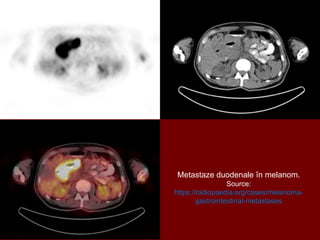

Metastaze gastrice și duodenale la un pacient cu melanom malign.

Source: https://radiopaedia.org/cases/melanoma-gastrointestinal-metastases

Metastaze duodenale în melanom.

Source:

https://radiopaedia.org/cases/melanoma-

gastrointestinal-metastases